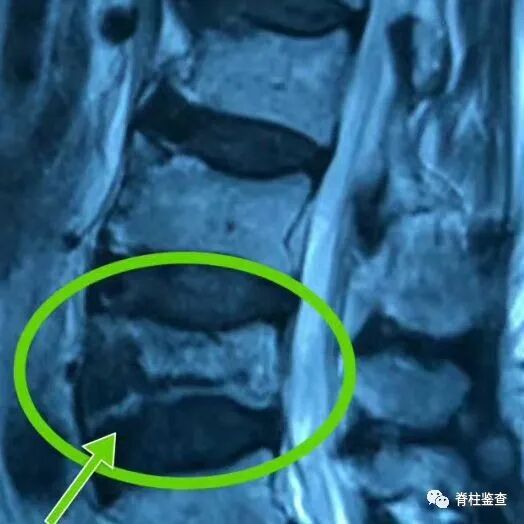

骨质疏松性椎体骨折Kümmell病